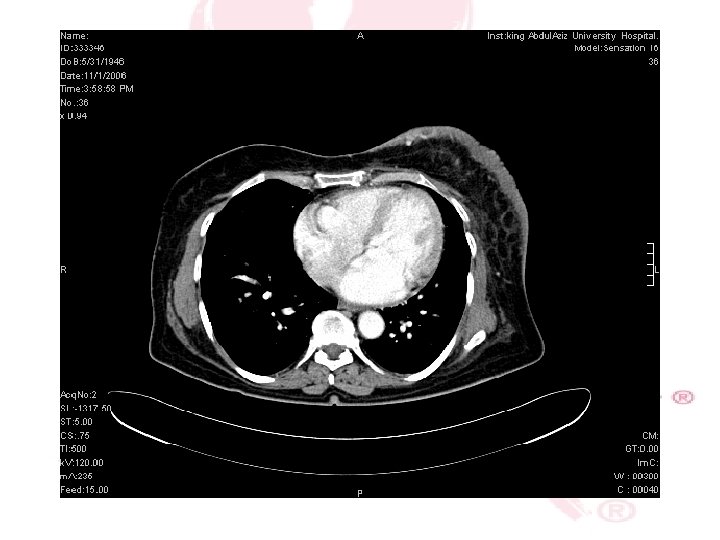

CT SCAN CHEST , ABDOMEN &PELVIS